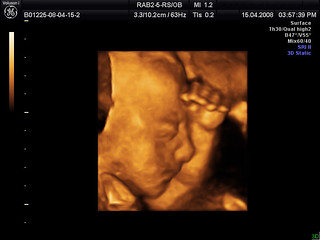

Ultrasonido 3D y 4D

Baby Bob in 3D - We went for our 4D ultrasound yesterday and… - FlickrLa ecografía 3D es útil para identificar ciertas anomalías congénitas, como irregularidades esqueléticas y problemas cardíacos, entre otras cosas. Este tipo de ultrasonido puede ayudar a controlar la frecuencia cardíaca del feto en tiempo real. Una frecuencia cardíaca anormal puede ser fatal. La frecuencia cardíaca se puede monitorear en tiempo real usando ultrasonido 3D en tiempo real.